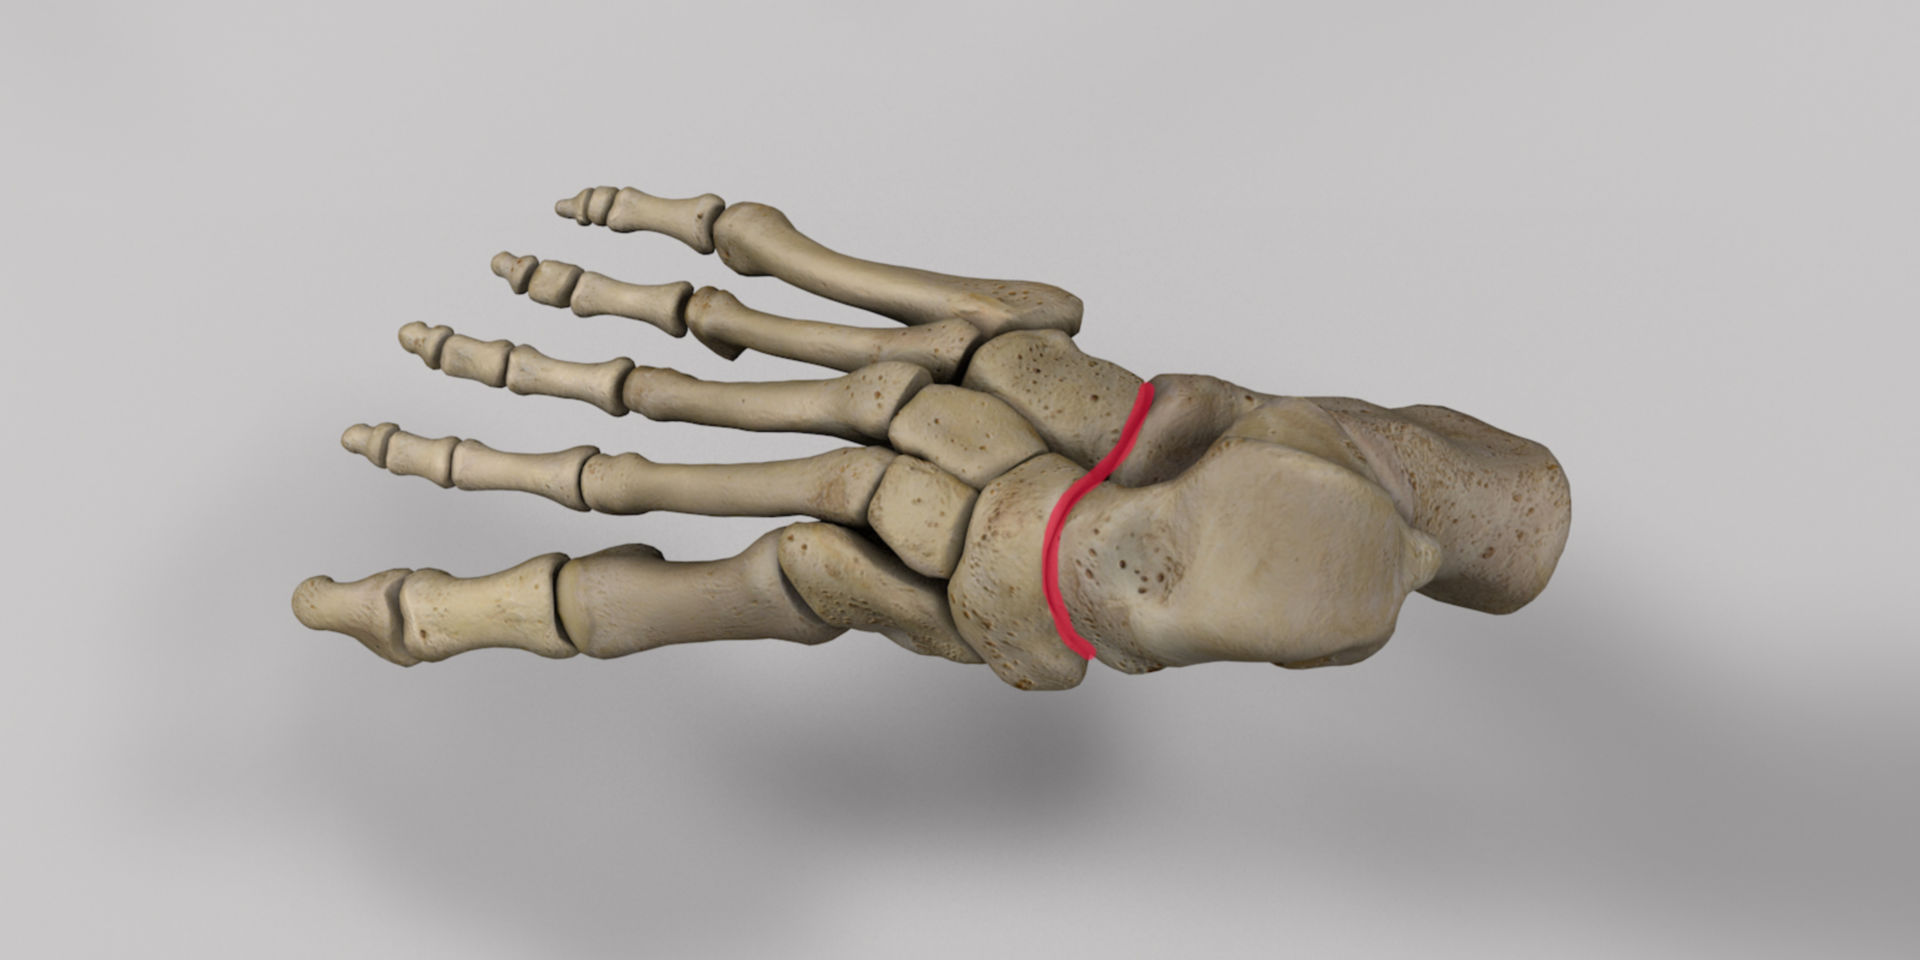

Анатомия суставов Шапарова и Лисфранка: фото и информация